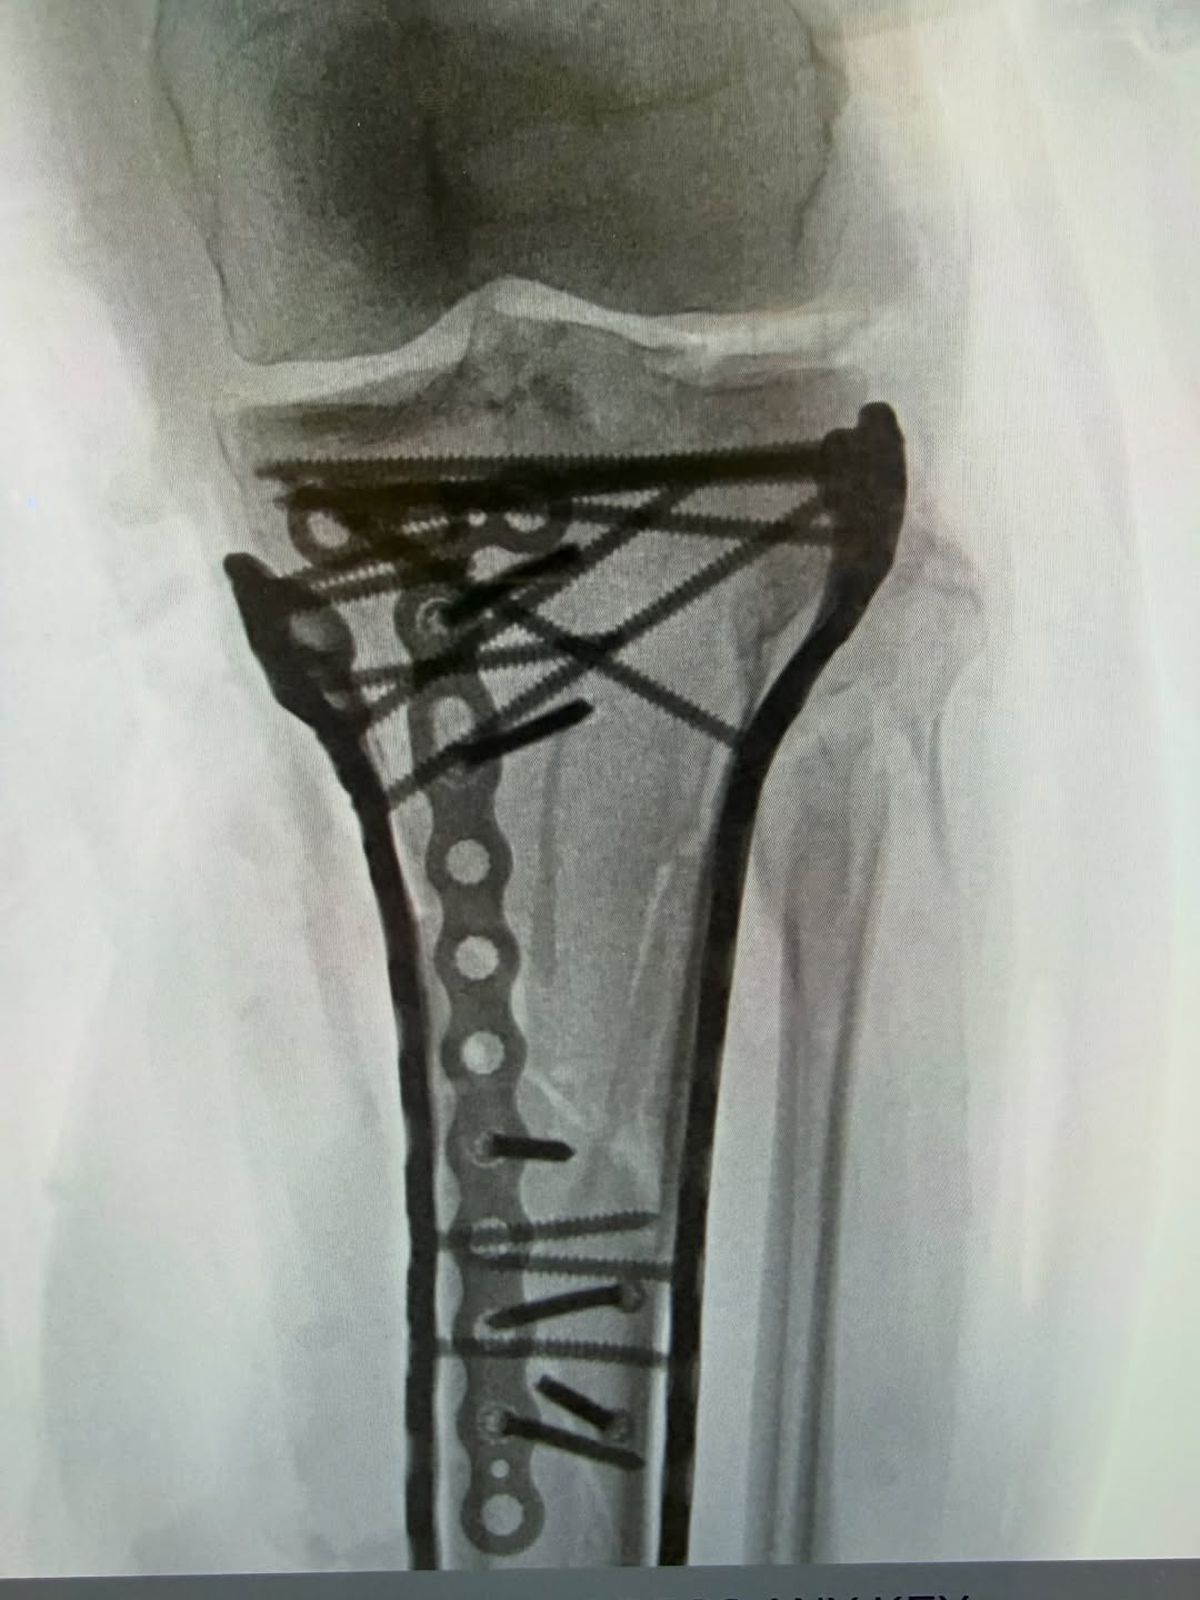

Foto 10/13 : Piciorul lui Lindsey Vonn după operația din 20 februarie // foto: Instagram